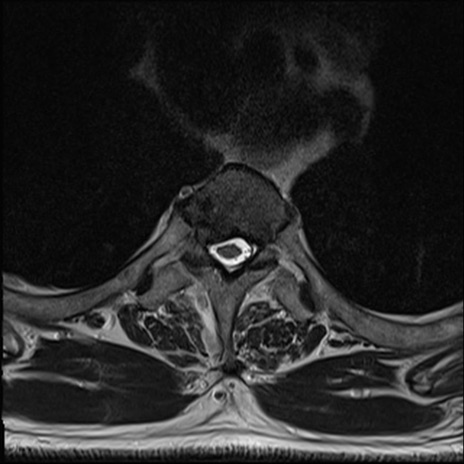

【整形】TIPS症例7 頚椎MRI T2WI(横断像)

頚椎MRI

矢状断像と横断像